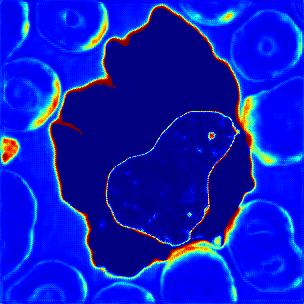

Figure 7: Visualization results of ATA-Module’s Attention Map: (a) Input image. (b-e) Attention map.

4.3.3 Visualization of ATA-Module

The attention maps of ATA-Module in AML-Net are visualized in Figure 7. When we select a cytoplasmic pixel as a reference, the cytoplasmic regions with high similarity are highlighted in red as shown in Figure 7. As shown in Figure 7, the attention map will respond only to cell nucleus and the other classes are blue with low similarity when cell nucleus is selected as a reference. In addition, as shown in Figure 7, when a pixel of an red blood cell which is a part of the background pixel is selected, only the similar red blood cells are reacted to not the entire background. Therefore, in Figure 7, it can be confirmed that red blood cells are not reacted when the pixels of the background other than red blood cells are selected. These results show that ATA-Module can enhance the similarity not only among the three classes; cytoplasm, cell nucleus and background, but also between red blood cells and other parts of the background. Based on these attention maps created from the discriminator, efficient leakage to the generator is performed.